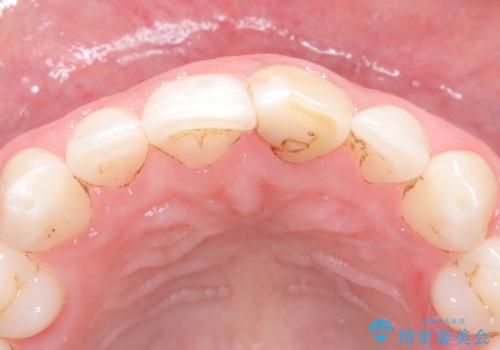

過去に神経の治療をした歯に変色がみられました。ラバーダム防湿の重要性を説明し、予防的に再根管治療から行い、被せ物をすることとなりました。

なるべく隣の歯と調和するようにしました。大変ご満足いただけました。